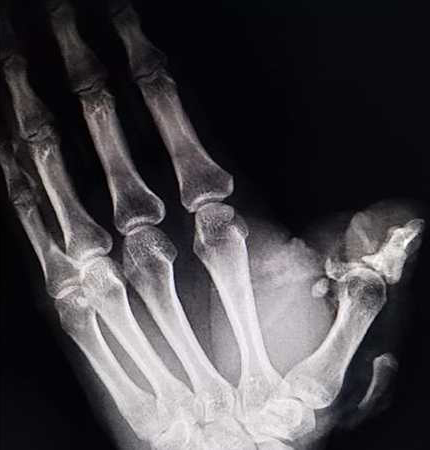

8月26日中午1时左右,我院急诊医学科收治一名由外院辗转至我院的“左拇指创伤性切割”患者,该患者在工作中左手不慎被电锯锯伤,左手拇指畸形,伤口活动性喷血,远端组织离断,局部组织毁损严重,手指活动障碍,远端肢体苍白无血运。患者万分焦虑,神情痛苦,情况不容乐观。

急诊医学科手外伤团队副主任刘路培、何居璘医生立即到位,经了解患者早上8点左右受伤,急忙赶到外院寻求帮助,因伤指毁损严重、治疗难度大、再植成活力低,首诊医院建议转到治疗条件好、救治水平高的柳州市人民医院就医。患者辗转来到我院已经是中午1点多,由于受伤时间长,患者对治疗逐渐失去了信心。两名医师查看病人的情况后,判断这种严重毁损的拇指撕脱离断伤,唯一可能恢复拇指功能的救治措施只有尽早再植,离断拇指越早手术,再植成功的几率就越大。为了病人,必须与时间赛跑,刘路培马上联系手术室团队开启急诊绿色通道,同时进行术前准备,组织急诊医学科专家制定最佳手术方案后,立即将患者送入手术室进行急诊断肢再植术。

患者实施麻醉后,刘路培、何居璘立即在显微镜下为患者的伤指进行精细清创,术中见患者创面严重污染,近节指骨及皮肤软组织毁损严重伴大面积皮肤撕脱,作为一名手外科医生,刘路培、何居璘接触过太多诸如此类的病例,显然这次的艰难程度远远超出以往。他们深知手指对于每个人而言有多重要,拇指功能的残缺不仅影响患者的工作生活,也会打击患者内心,常常感到自卑,所以整个团队同心协力要保住患者的拇指。专家团队默契配合,根据患者伤指条件术中再次调整手术方案,首先处理指骨缺损,用残存的骨头拼接恢复指骨的骨量,复位骨折,然后用微型钢针小心的将骨头固定起来,恢复了拇指的力线与角度,紧接着在显微镜下用比发丝还细的显微血管缝线吻合指背静脉、指固有动脉及神经,最后处理撕脱皮肤,一针一线都是那么仔细、完美。松止血带后离断拇指终于又恢复了正常血运,拇指颜色由苍白变成红润、血运良好!手术顺利结束,患者安全送回病房。